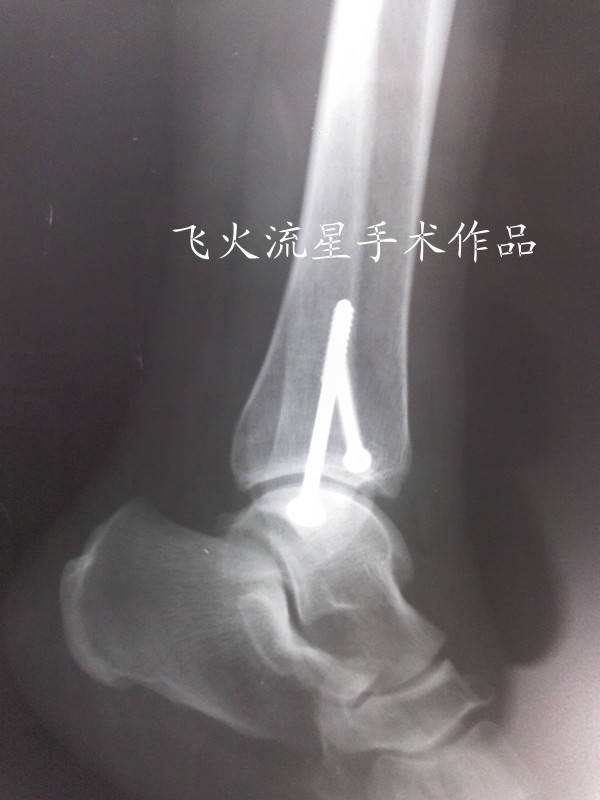

内踝进钉前术者应该用了骨钻打空,估计是怕打进关节腔吧,所以打的高了些再或是暴露不够。

其实内踝用普通松质骨螺钉固定时可以不用骨钻,直接用2.0或2.5的克氏针做一个锥子复位后直接在上面钻孔后拧钉即可。此办法简单有效,本人一直在使用,效果很好。